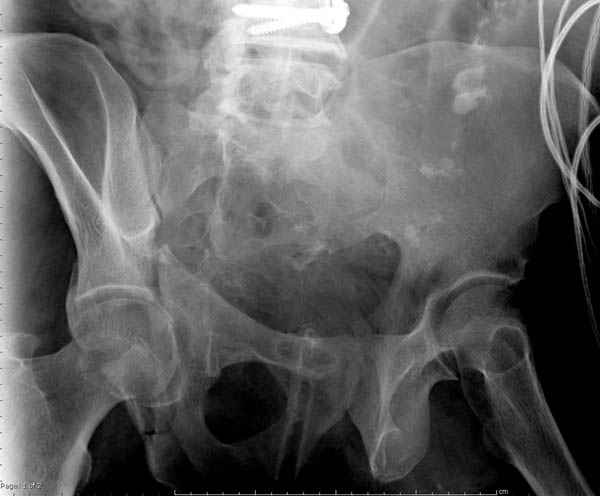

Вложение не в текстовом формате было извлечено…

Имя     : 2 Proximal hum+acetabulum Judet iliac.jpg

Тип     : image/jpeg

Размер  : 26064 байтов

Описание: отсутствует

Url     : http://weborto.net:8080/pipermail/ortho/attachments/20071130/37ea88e5/attachment-0009.jpg